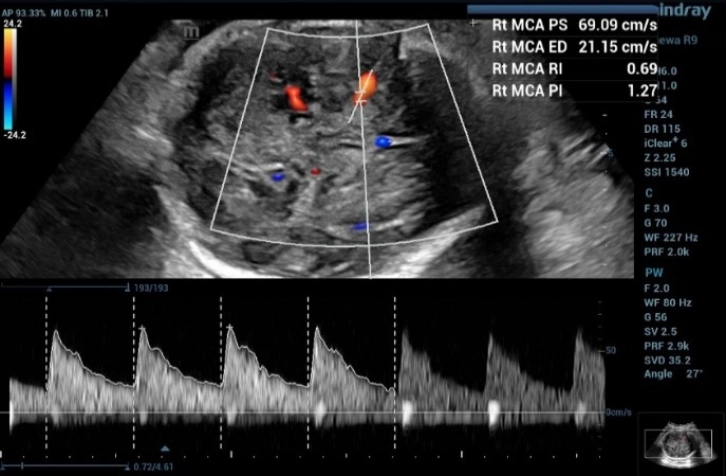

2. Middle Cerebral Artery Doppler for fetal anemia (Hb Bart's disease)

Fetal middle cerebral arterial (MCA) Doppler assessment is an important part of assessing fetal cardiovascular distress, fetal anemia or fetal hypoxia. In the appropriate situation it is a very useful adjunct to umbilical artery doppler assessment.

From the three MCA-PSV measurements in this fetus,

1st MCA-PSV= 69.09 = 1.833 MoM (Figure 4)

the first measurement of the doppler waveform of MCA in fetus with and the MCA-PSV value was 69.09 cm/s, which is greater than 1.55 MoM

Figure 4 Shows the first measurement of the doppler waveform of MCA in fetus with and the MCA-PSV value was 69.09 cm/s, which is greater than 1.55 MoM